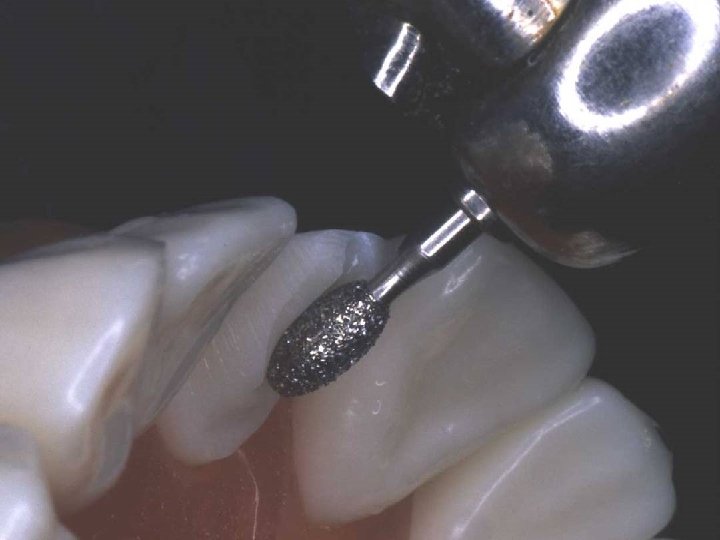

Depth-orientation grooves

Incisal reduction

Incisal facial reduction

Gingival facial reduction

Initial proximal reduction